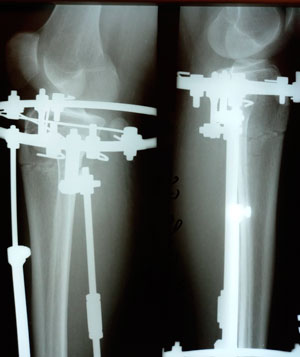

перед крутками

Вложения

image-05-02-21-07-28-1.jpg